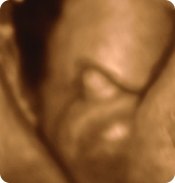

havde taget et lille emne op igår omkring min fortvivelse på om det her 3D billede fra uge 16 ikke ligner en lille 'tap' ? trods hende der scannede mig mente at havde det været en dreng havde den lille tap været større?? men nogle ser allerede tappen fra 14 uge så er meget forvirret .. til MD scanningen i uge 19 mente de pige - men sagde jeg skulle få tjekket det til næste scanning. problemet er jeg ik er henvist til flere.Og hvis det er en dreng har jeg købt det helt forkerte hjem

HVIS det er en pige har jeres lille så også haft det mellem benene og hvis det har været dreng har den så været større???

Vedhæftede fotos (klik for at se i fuld størrelse)